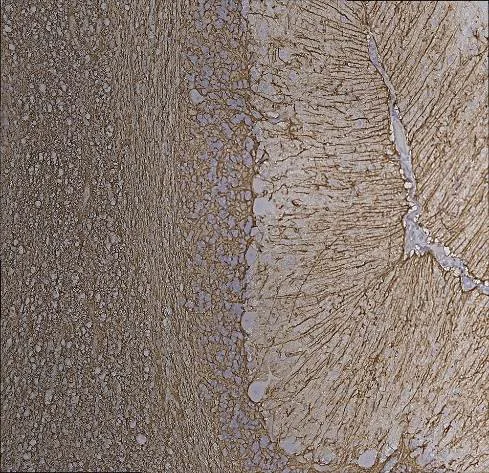

Immunohistochemistry (Formalin/PFA-fixed paraffin-embedded sections) - Anti-GFAP antibody [2A5] - Astrocyte Marker (AB4648)

Immunohistochemistry analysis of paraffin-embedded human cerebellum tissue sections labelling GFAP with ab4648 at 1/500 dilution (1 mg/mL). Sections were stained with ab4648 using the HRP/DAB staining. Sections were counterstained with hematoxylin/eosin. Antigen retrieval was heat mediated using Antigen retrieval buffer (100X citrate buffer) (pH 6.0) (ab93678) for 15 minutes.

TTo the right is a region of cerebellar molecular layer containing the prominent cytoskeletal fibers of Bergmann glia which are strongly positive for GFAP. The middle shows a region of the granular layer and to the left is white matter, both of which contain GFAP positive astrocytes. The immunostaining was performed with the Vector ImmPress rat adsorbed horse anti-mouse IgG detection kit.